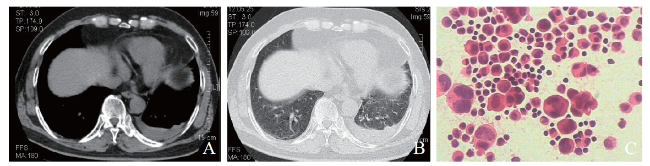

例4 患者男,39岁。因右侧胸背痛9 d于2018年7月9日收入我科。9 d前患者无明显诱因出现右侧持续性胸背痛,无胸闷、发热、心悸。当地医院予头孢呋辛联合左氧氟沙星抗感染及止痛治疗,7月7日当地医院胸部CT示右肺中下叶炎症,右侧胸膜增厚伴少量胸腔积液。起病以来,患者无皮疹、盗汗等,近1周体质量下降4 kg。既往史及个人史无特殊。入院体格检查:体温 37.1 ℃,脉搏 96次/分,呼吸 20次/分,血压125/85 mm Hg。双肺呼吸音粗,右下肺可闻及少许细湿啰音。入院后查血常规示:血红蛋白137 g/L,白细胞6.62×109/L, 血小板291×109/L,凝血酶原时间、活化部分凝血活酶时间、凝血酶时间、纤维蛋白原均正常,D二聚体正常。自身免疫相关指标:抗心磷脂抗体IgG(+),核周型-抗中性粒细胞胞浆抗体(+),抗核抗体颗粒型(+),抗双链DNA抗体(+)。入院后予哌拉西林钠-他唑巴坦钠4.5 g、每8 h 1次静脉滴注,未见明显好转。7月18日胸部CT示:①右下肺动脉及其分支栓塞;②右肺下叶炎性病变,部分较前吸收,部分范围较前增大(图4),建议继续治疗后复查;③右侧胸腔少量积液,较前吸收。右肺下叶见多发不规则片状影,边界欠清,增强扫描强化不明显(图4A、B)。7月12日BAL液基细胞学及涂片可见较多泡沫样组织细胞(图4C)。考虑SLE合并抗磷脂抗体综合征及肺栓塞,予甲泼尼龙40 mg、每日1次,羟氯喹0.2 g、每日2次,甲氨蝶呤10 mg、每周1次及利伐沙班10 mg、每日2次抗凝治疗,患者症状好转出院。至撰稿日长期门诊随访,治疗效果良好,未再出现胸痛等不适症状。

图4 例4 SLE合并抗磷脂抗体综合征及肺栓塞患者的胸部CT及BAL涂片结果

A:胸部CT纵隔窗;B:胸部CT肺窗;C:BAL涂片(HE染色,×400)